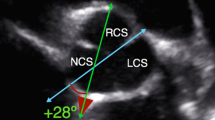

Transthoracic echocardiography was performed using the Vivid E95 and Vivid S6 ultrasound systems and M5Sc or 6S transducers manufactured by General Electric, Boston, MA. Each echocardiogram was conducted by an experienced cardiologist in accordance with the recommendations of the European Association of Cardiovascular Imaging (EACVI) and the American Society of Echocardiography (ASE) [12]. The aortic root was shown using two-dimensional echocardiography in the parasternal long-axis view. The maximum dimension of the aortic root was measured in millimeters at the sinuses of Valsalva, perpendicular to the long axis of the aorta. Both the above-mentioned documents (EACVI and ASE) recommend the leading edge in end-diastole technique for aortic root measurements. However, in the child population, no uniform method has been established to date for aortic root measurement and there are different nomograms. Therefore, in this study, we performed aortic root measurements using two different techniques: the leading edge in end-diastole and inner edge in mid-systole (Fig. 1a–d).